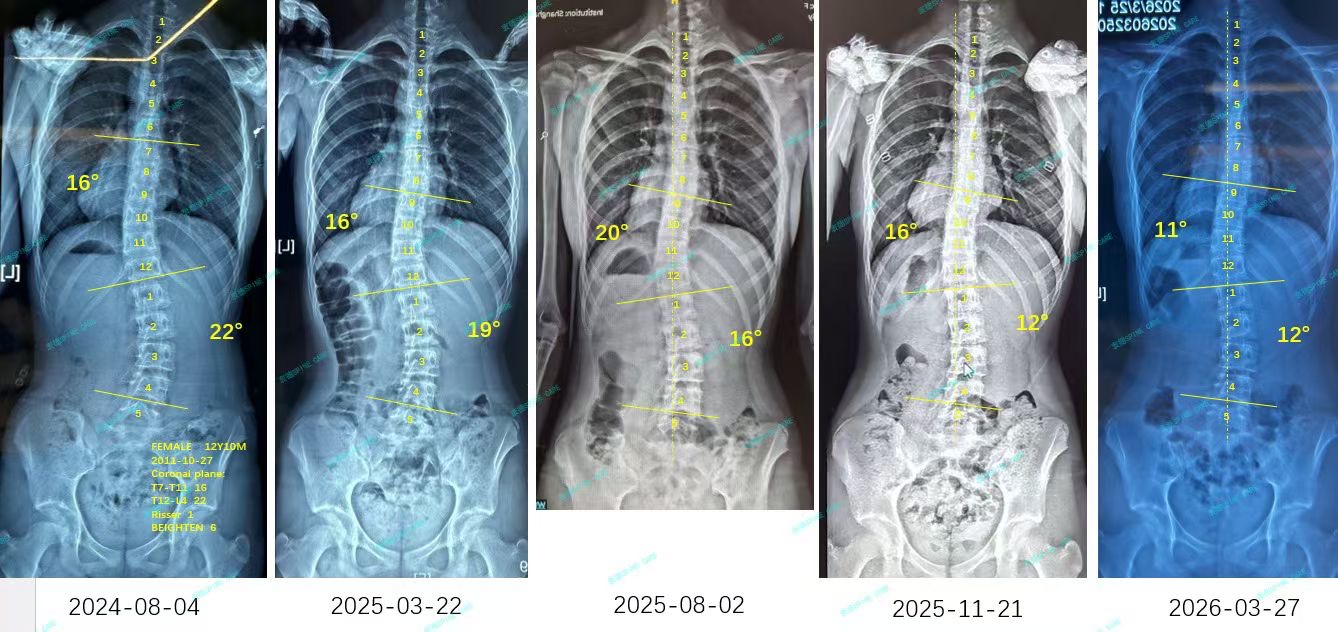

来自家长对衷德的评价(曦曦妈妈)

衷德脊柱,我们只关注侧弯保守治疗~

Zhongde Spine, bending no breaking ~